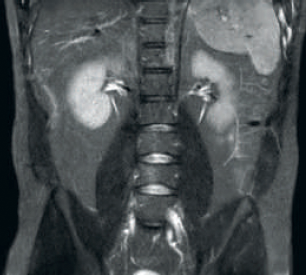

Resultado: resolución de imagen y SNR mejoradas

Resultado: imágenes ruidosas que usan parámetros de exploración idénticos

La tecnología de recepción de RF dStream digitaliza la señal del resonador magnético directamente en la bobina de radiofrecuencia, lo que resulta en un aumento de hasta un 40 % más de la SNR* en todo el volumen de la imagen.